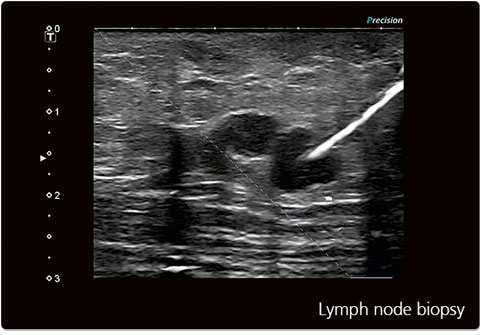

La biopsie sous échographie est un acte de radiologie interventionnelle réalisé sous guidage échographique permettant de prélever un fragment de tissu à des fins diagnostiques, avec une grande précision et une sécurité optimale.

• Biopsie ganglionnaire

L’examen est réalisé en ambulatoire, sous anesthésie locale. Le guidage échographique permet un positionnement précis de l’aiguille et limite les risques de complications. La durée moyenne est de 15 à 30 minutes.